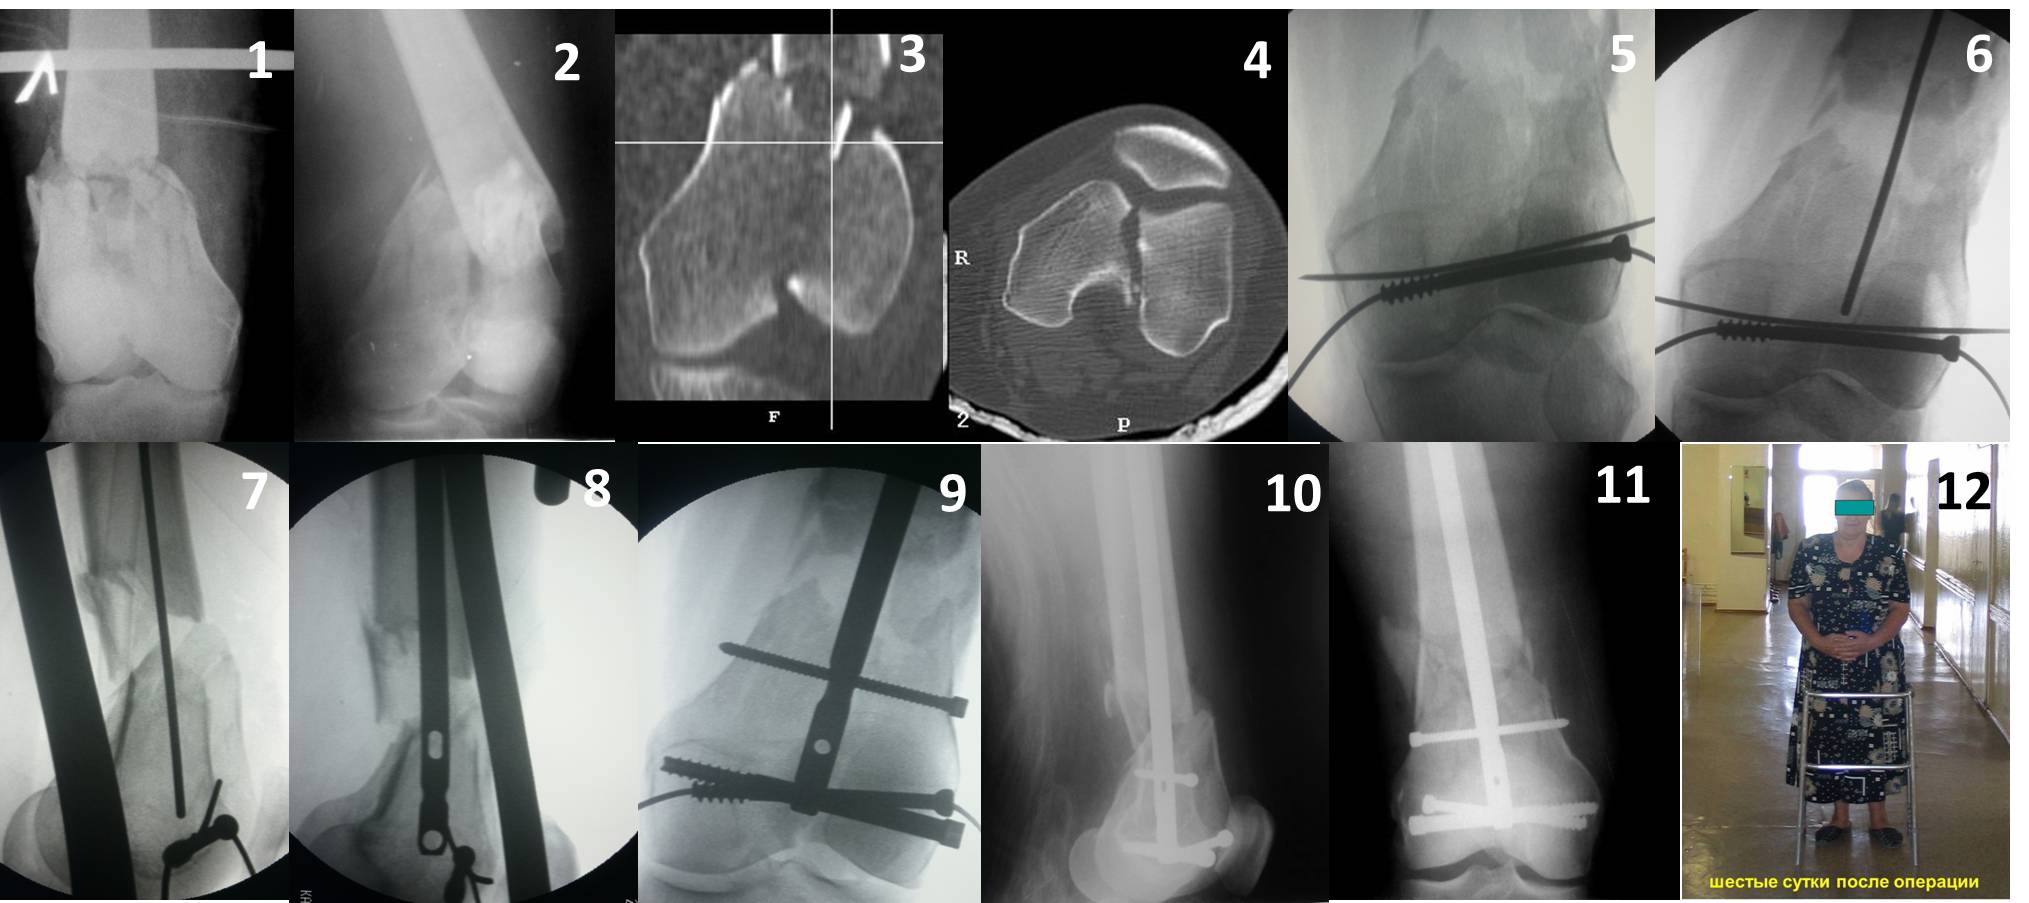

В приложении пример недавней операции, C3, открытая репозиция, фиксация мыщелков спицами и винтами, ретроградный синтез большеберцовым гвоздем 10,5 мм диаметром, винты 5 мм.

Рационально ориентироваться на качественный аспект - проблема или решается, или нет. Переломы типа 33C1 или C2 (то есть без фронтального раскалывания мыщелков, как на показанной Вами томограмме) при обычном качестве кости успешно можно фиксировать гвоздями с фронтальными винтами. Получается, их прочностных характеристик уже достаточно.

Такое проведение винтов становятся критически важным при переломах типа C3. Где, как правило, без открытой репозиции не обойтись. И пластины тут предлагают больше возможностей - и винтов много, и полиаксиально можно вводить. Иногда гвозди тоже получается использовать. Раз уж колено открыли, то через него и ввести проще, и винты в разных плоскостях с кондуктором удобнее вводить. Так что ретроградные становятся привлекательнее. И большеберцовые, кстати, в качестве ретроградных бедренных очень хорошо использовать.